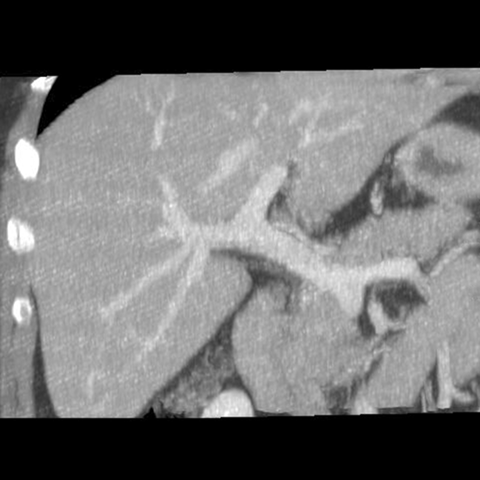

Portal Venous System, CT ( coronal ) [5 of 5]